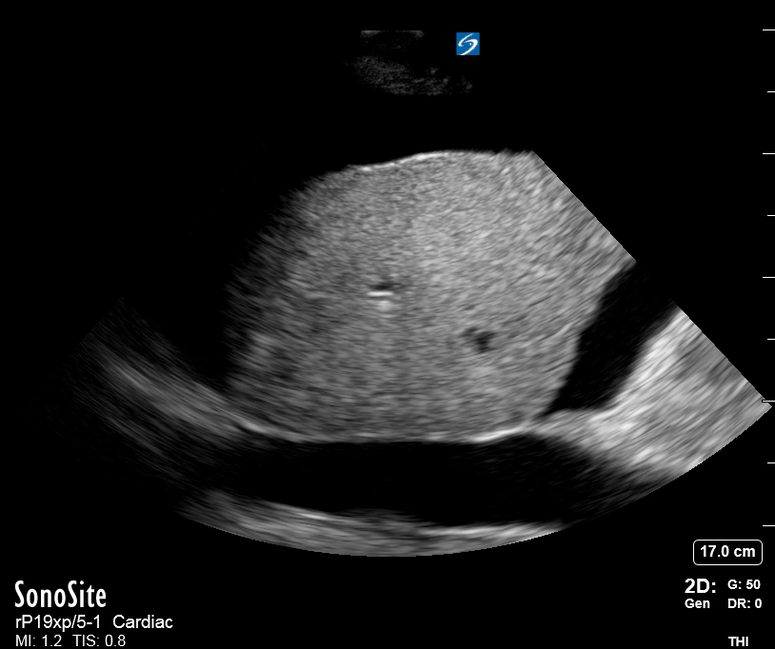

Entrance: is there evidence of low preload?

The IVC diameter changes depending on intravascular volume status, and normally, the IVC collapses during spontaneous inspiration. Therefore, the IVC diameter represents a non-invasive method for estimating central venous pressure (CVP). The evidence suggests that in spontaneously breathing patients, there is a good correlation between the sonographic estimation of CVP and values measured with invasive methods (2). IVC filling and CVP, however, allow only a rough correlation with volume status, and the sonographic estimation of preload should at least include the assessment of the LV and the Lung. Thus, it is better to think of IVC filling as an indicator of fluid tolerance, instead of a determinant of fluid responsiveness (6).

IVC exploration is best from the subxiphoid approach with longitudinal and transverse images. The IVC should be assessed in terms of overall size and collapsibility. The diameter is typically measured at its largest (end of expiration) at 1-2 cm distal to where the hepatic veins join the vena cava. An IVC diameter of ≥ 2 cm, especially with minimal or no collapsibility, is considered plethoric and correlates with increased RA pressure. An IVC of < 1 cm, particularly with complete collapse, is considered flat and indicates low preload and potential fluid responsiveness. An IVC diameter between 1 and 2 cm is typically normal.

PITFALLS

In a long-axis view, beware of not sliding off the centre of the vessel, as this will underestimate the size of the IVC and overestimate its collapse. Obtaining long and short axis views may help avoid this pitfall. Another mistake is confusing the descending aorta for the IVC, particularly when scanning in long-axis. Although the IVC may appear to pulsate, the aorta has a thicker wall, and its position is to the patient’s left. Following the IVC upwards will reveal the hepatic veins junction and the entrance to the RA, while the aorta will travel behind the heart. The IVC moves both anterolaterally and craniocaudally with inspiration, and this should be considered during visualization or measuring. For this very reason, measuring in M-mode is not recommended as it would not be accurate.

SHOCK

In a shocked patient, a flat or highly collapsible IVC correlates well with low preload estates (hypovolaemia, haemorrhage, sepsis). Yet by itself, a small IVC is not enough to define low preload and could also represent a normal finding.

Conversely, a distended, not collapsing IVC suggests distal obstruction in a shocked patient. Potential causes include LV failure, massive PE, tension pneumothorax and cardiac tamponade. Nonetheless, there are other causes of elevated cava / RA pressure, such as chronic pulmonary hypertension.